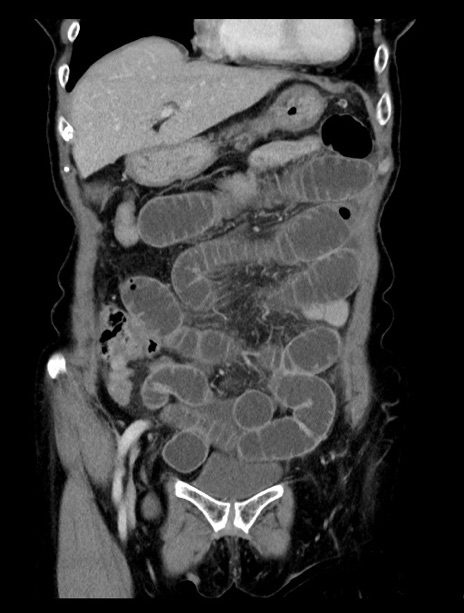

症例23(冠状断像)

【症例】70歳代女性

【主訴】下腹部痛・嘔吐

【現病歴】2日前より腹痛あり。昨日嘔吐あり。症状改善しないため来院。

【既往歴】胃GISTに対して胃部分切除後。

【身体所見】BT 37.1℃、BP 128/77mmHg、腹部:平坦・軟、下腹部に圧痛あり。

【データ】WBC 10200、CRP 0.31